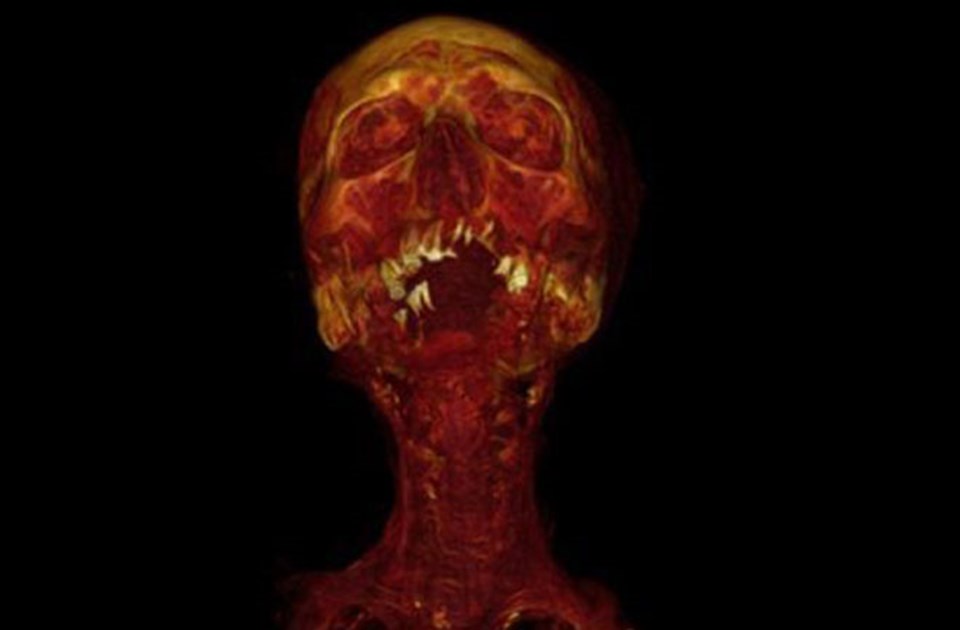

Hatiay adlı mumyanın bilgisayarlı tomografide beliren 3D görüntüsü.

Hatiay adlı mumyanın bilgisayarlı tomografide beliren 3D görüntüsü.